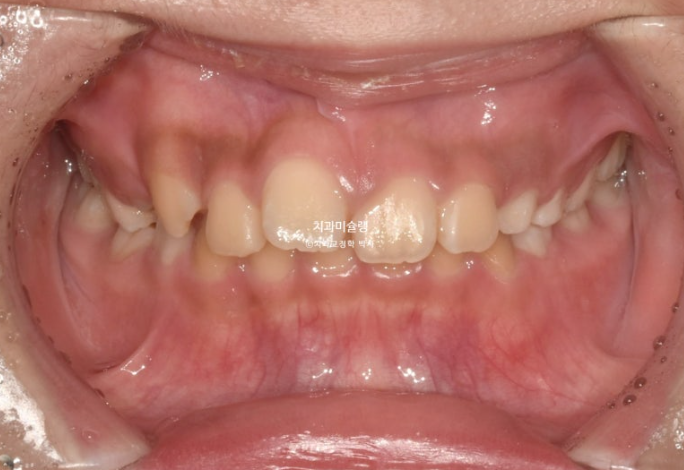

2년 전 교정치료를 위해 온 만 10세 어린이 입니다.

앞니가 하나 들려있고 깊게 물리는 과개교합이 있습니다.

중심선 불일치도 보입니다.

윗니 돌출이 측면에서 잘 보이네요.